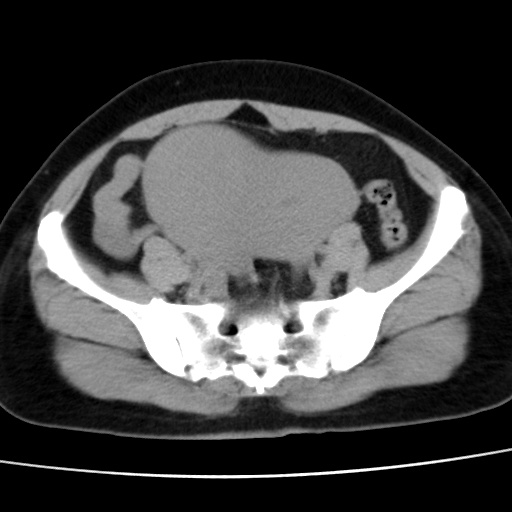

子宫多发肌瘤吗

多发性子宫肌瘤.

考虑多发子宫肌瘤,子宫直肠窝双囊性占位,另直肠周围脂肪密度增高,不知有何病史

支持考虑多发子宫肌瘤~!子宫直肠陷凹积液?

支持考虑多发子宫肌瘤~!子宫直肠陷凹积液!

子宫肌瘤,宫体部后方见液性密度影,是肠道还是子宫与直肠陷窝积液不好说,我觉得它的位置有点高

支持考虑多发子宫肌瘤!子宫直肠陷凹积液!

患者发热,而子宫直肠窝液性灶有明显边缘且局限且囊性,不除外为包裹性积液或脓肿

支持考虑多发子宫肌瘤,子宫直肠陷凹积液可能。

考虑多发子宫肌瘤

1)考虑子宫肌瘤可能性大。2)子宫后方囊性占位性病变,不排除卵巢囊肿可能。

考虑多发子宫肌瘤。子宫后方囊性占位性病变,不排除卵巢囊肿可能。